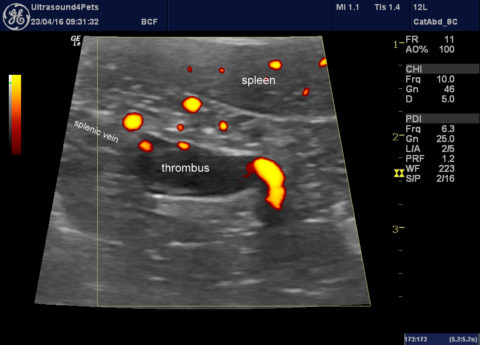

Another anaphylactic shock dog

This is my own dog -I’m feeling able to write this now that he’s recovered fully. As previously discussed anaphylaxis is a phenomenon which can be difficult to document definitively. However, like the last case which I wrote up a few weeks back this involved a previously 100% healthy dog with a wasp/bee chasing habit … Continue reading